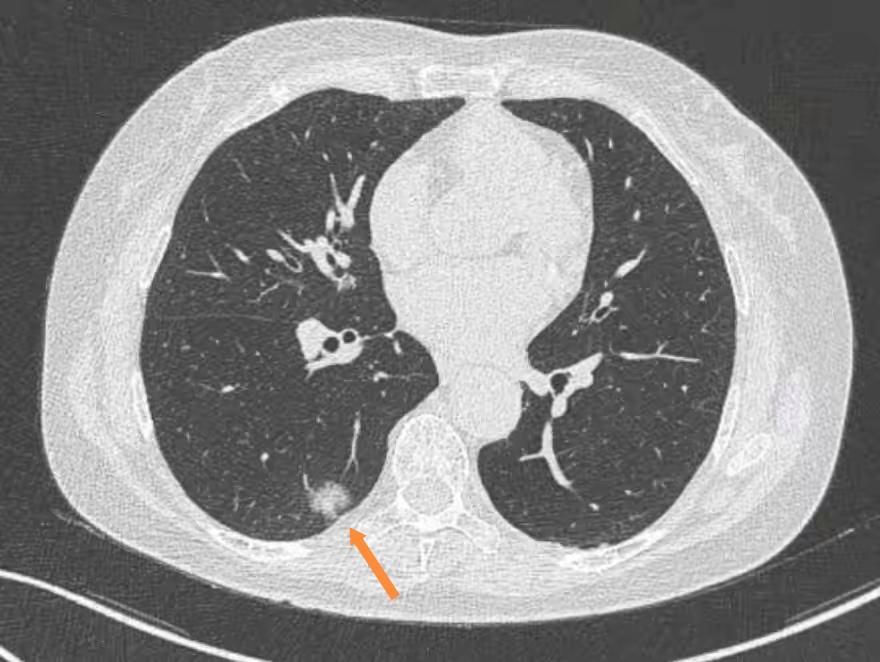

大小:直径≥8mm气象:分叶状、毛刺征、胸膜牵拉密度:羼杂磨玻璃结节,且实性身分在增大

随访中结节彰着增大:比如半年内直径增大≥2mm,或实性身分彰着加多